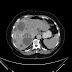

Fall 55: Akute Cholecycstitis? Mitnichten! - CT Befund

Fortsetzung von: http://notfallambulanz.blogspot.de/2016/05/fall-55-akute-cholecycstitis-mitnichten.html Sie denken an Leberfiliae! N...

Fall 55: Akute Cholecycstitis? Mitnichten!

Zur Aufnahme kommt eine 62-jährige Patientin in gutem AZ und reduziertem EZ. Sie klagt über seit dem Vorabend bestehende Flankenschmerzen r...